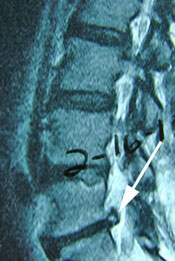

- Case Report: Lumbar Spine Post-Surgery

Probably no area of chiropractic spinal manipulation is as challenged as treating the post-surgical patient who is the same, worse, or disenchanted with their surgical outcome. Certainly, the opportunity to treat the patient before surgical intervention is best. When confronted with this post-surgical patient, however, the chiropractic physician proceeds as if with a patient who has not had surgery. i.e. The chiropractor will proceed with the careful history and clinical examination to determine what is causing the pain. That cause may be within the surgical site or adjacent to it. In treating the post-surgical spine, fusion or no fusion is a dictator of care. If there is a fusion, spinal manipulation is given to adjacent levels of the spine to the fused area. If there is no fusion, the doctor carefully proceeds as if no surgery. Some motion may be possible within the spine depending on the surgical procedure performed. (11)

Let’s look at some factors of interest and importance to a patient seeking chiropractic care for their post-surgical spinal problem. (11)